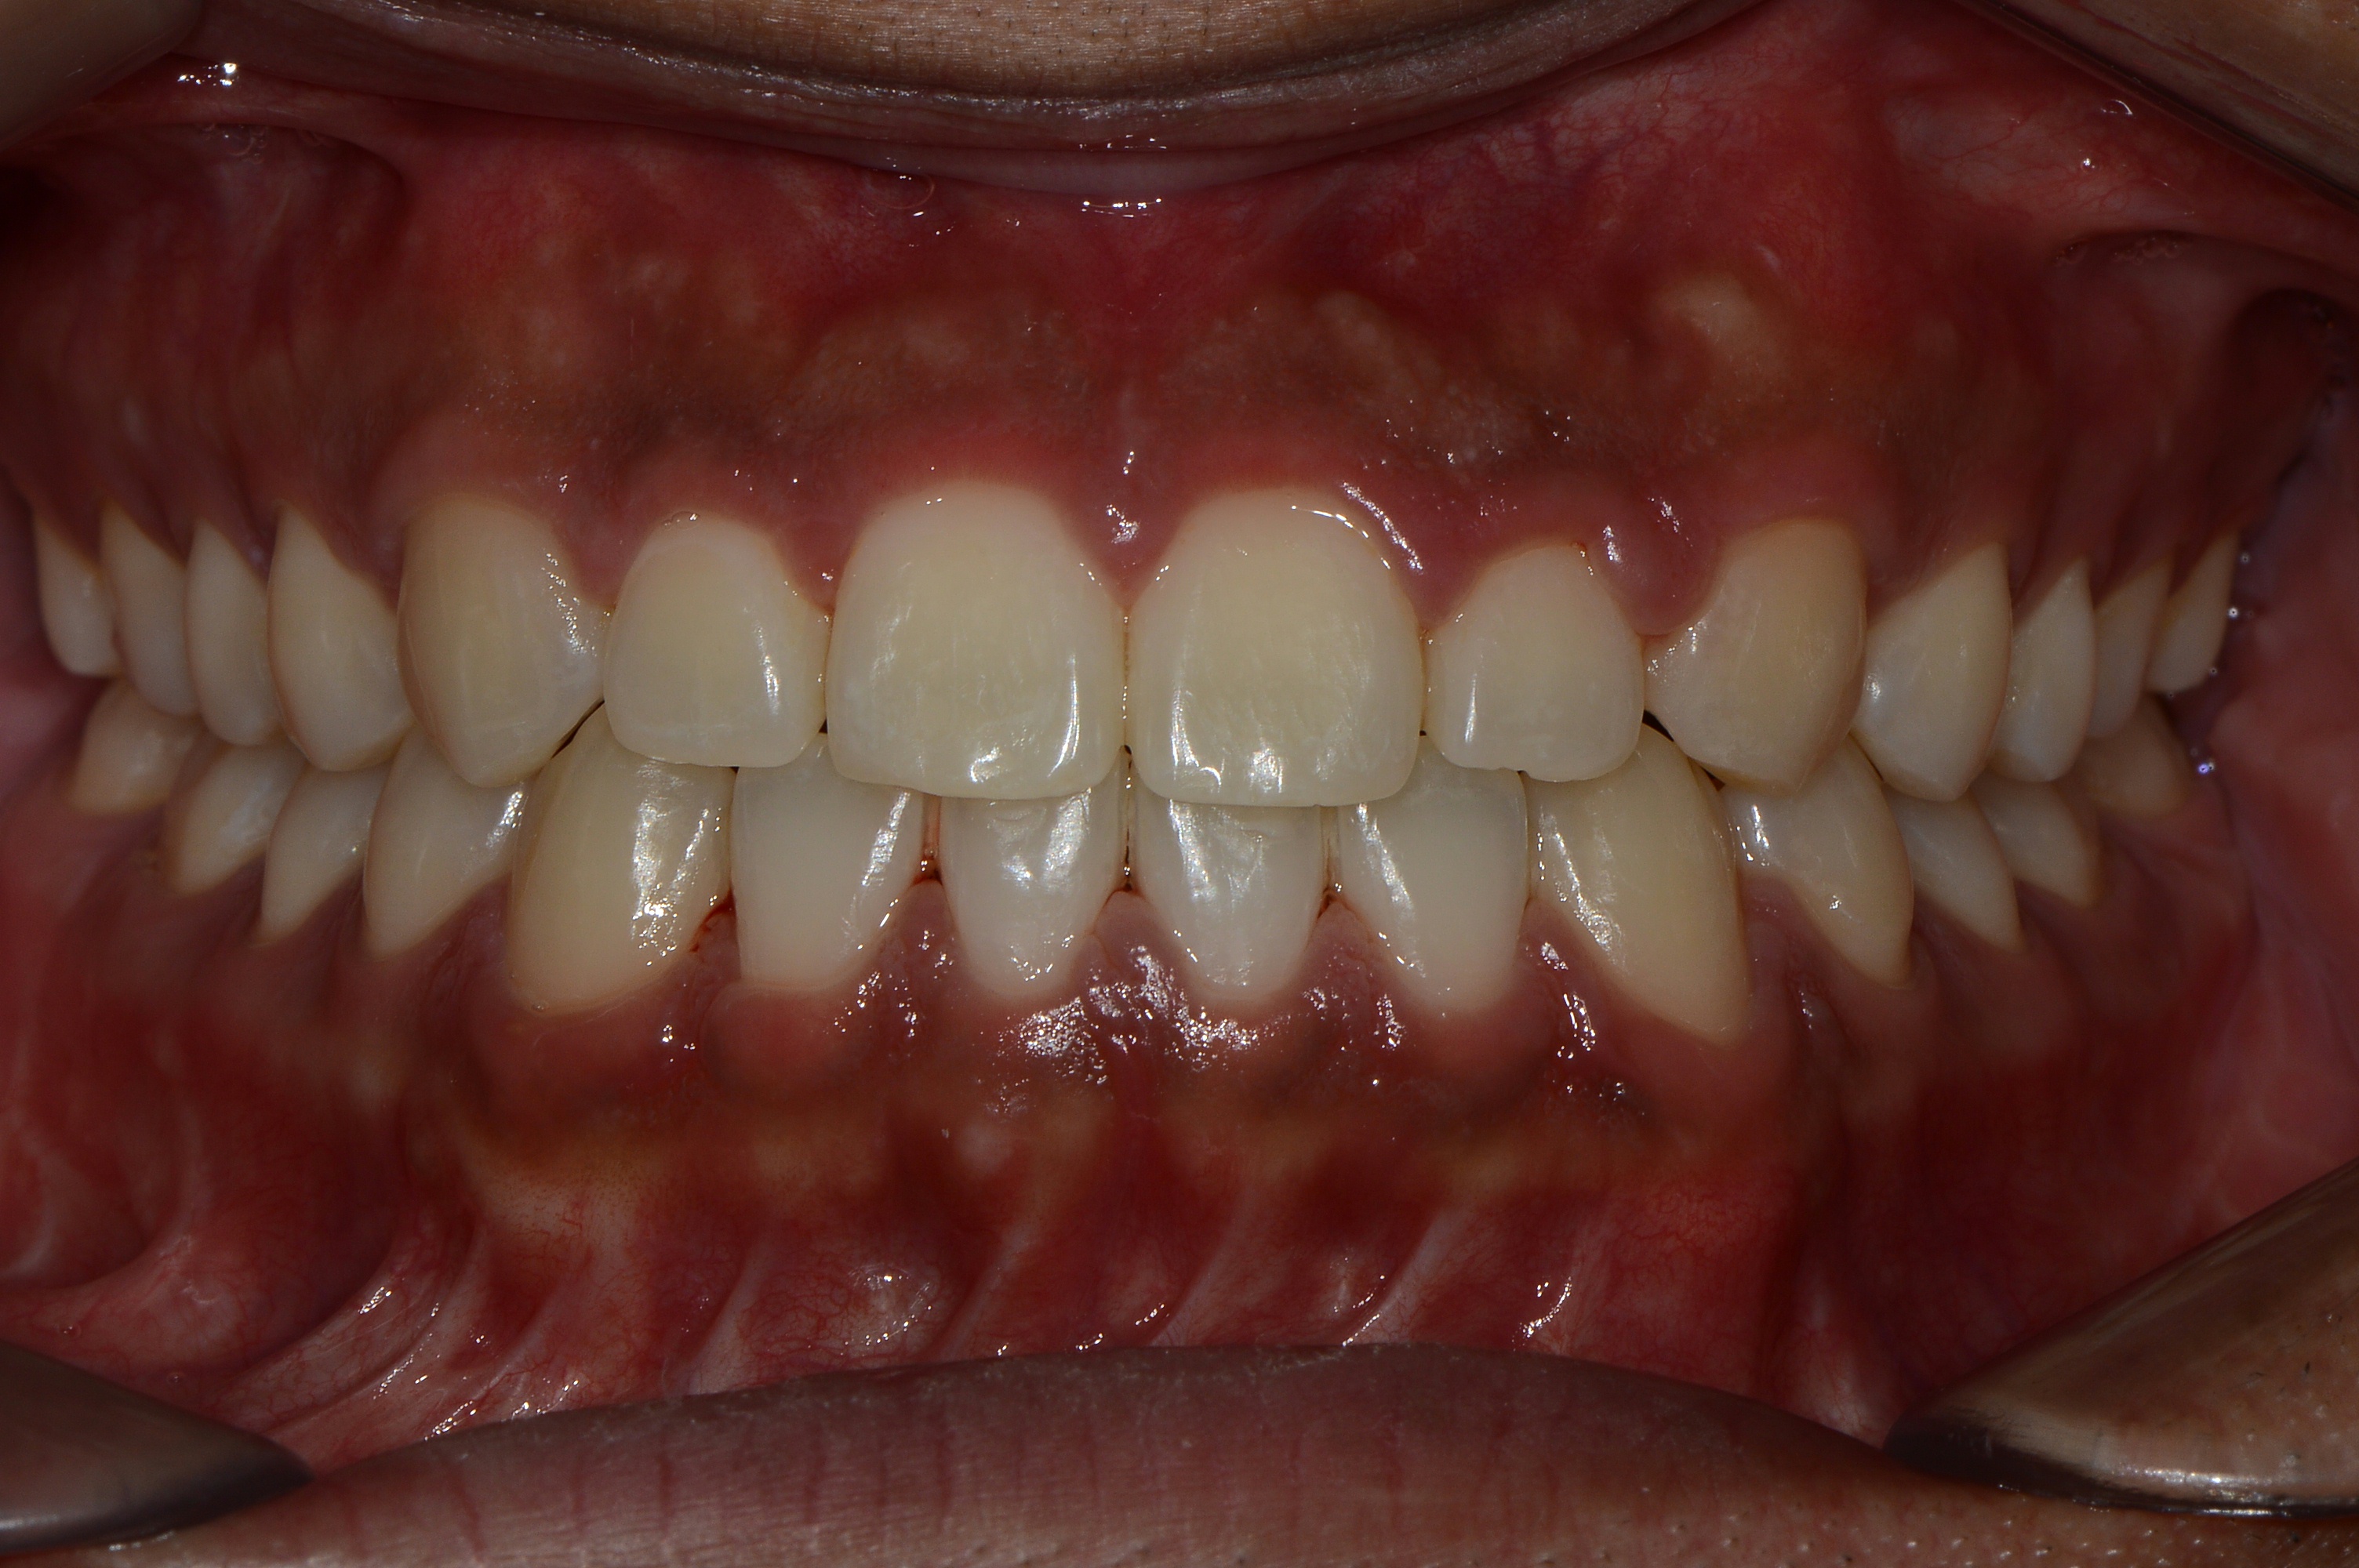

치료 후 사진입니다.